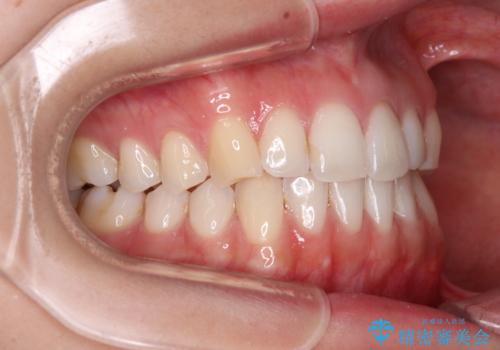

前歯の重なりをインビザライン・モデレートで矯正治療

- 上下前歯の重なりを気にして来院された患者様です。

安価なインビザラインパッケージを用いての治療を希望されており、デコボコの程度が中等度であったため、インビザライン・モデレートを用いて矯正治療を行うこととしました。

インビザライン・モデレートは、製作できるアライナーの枚数に制限があるため、移動可能な量に限りがあるものの、インビザライン・ライトよりも枚数が多いため、幅広い症例に対応可能です。